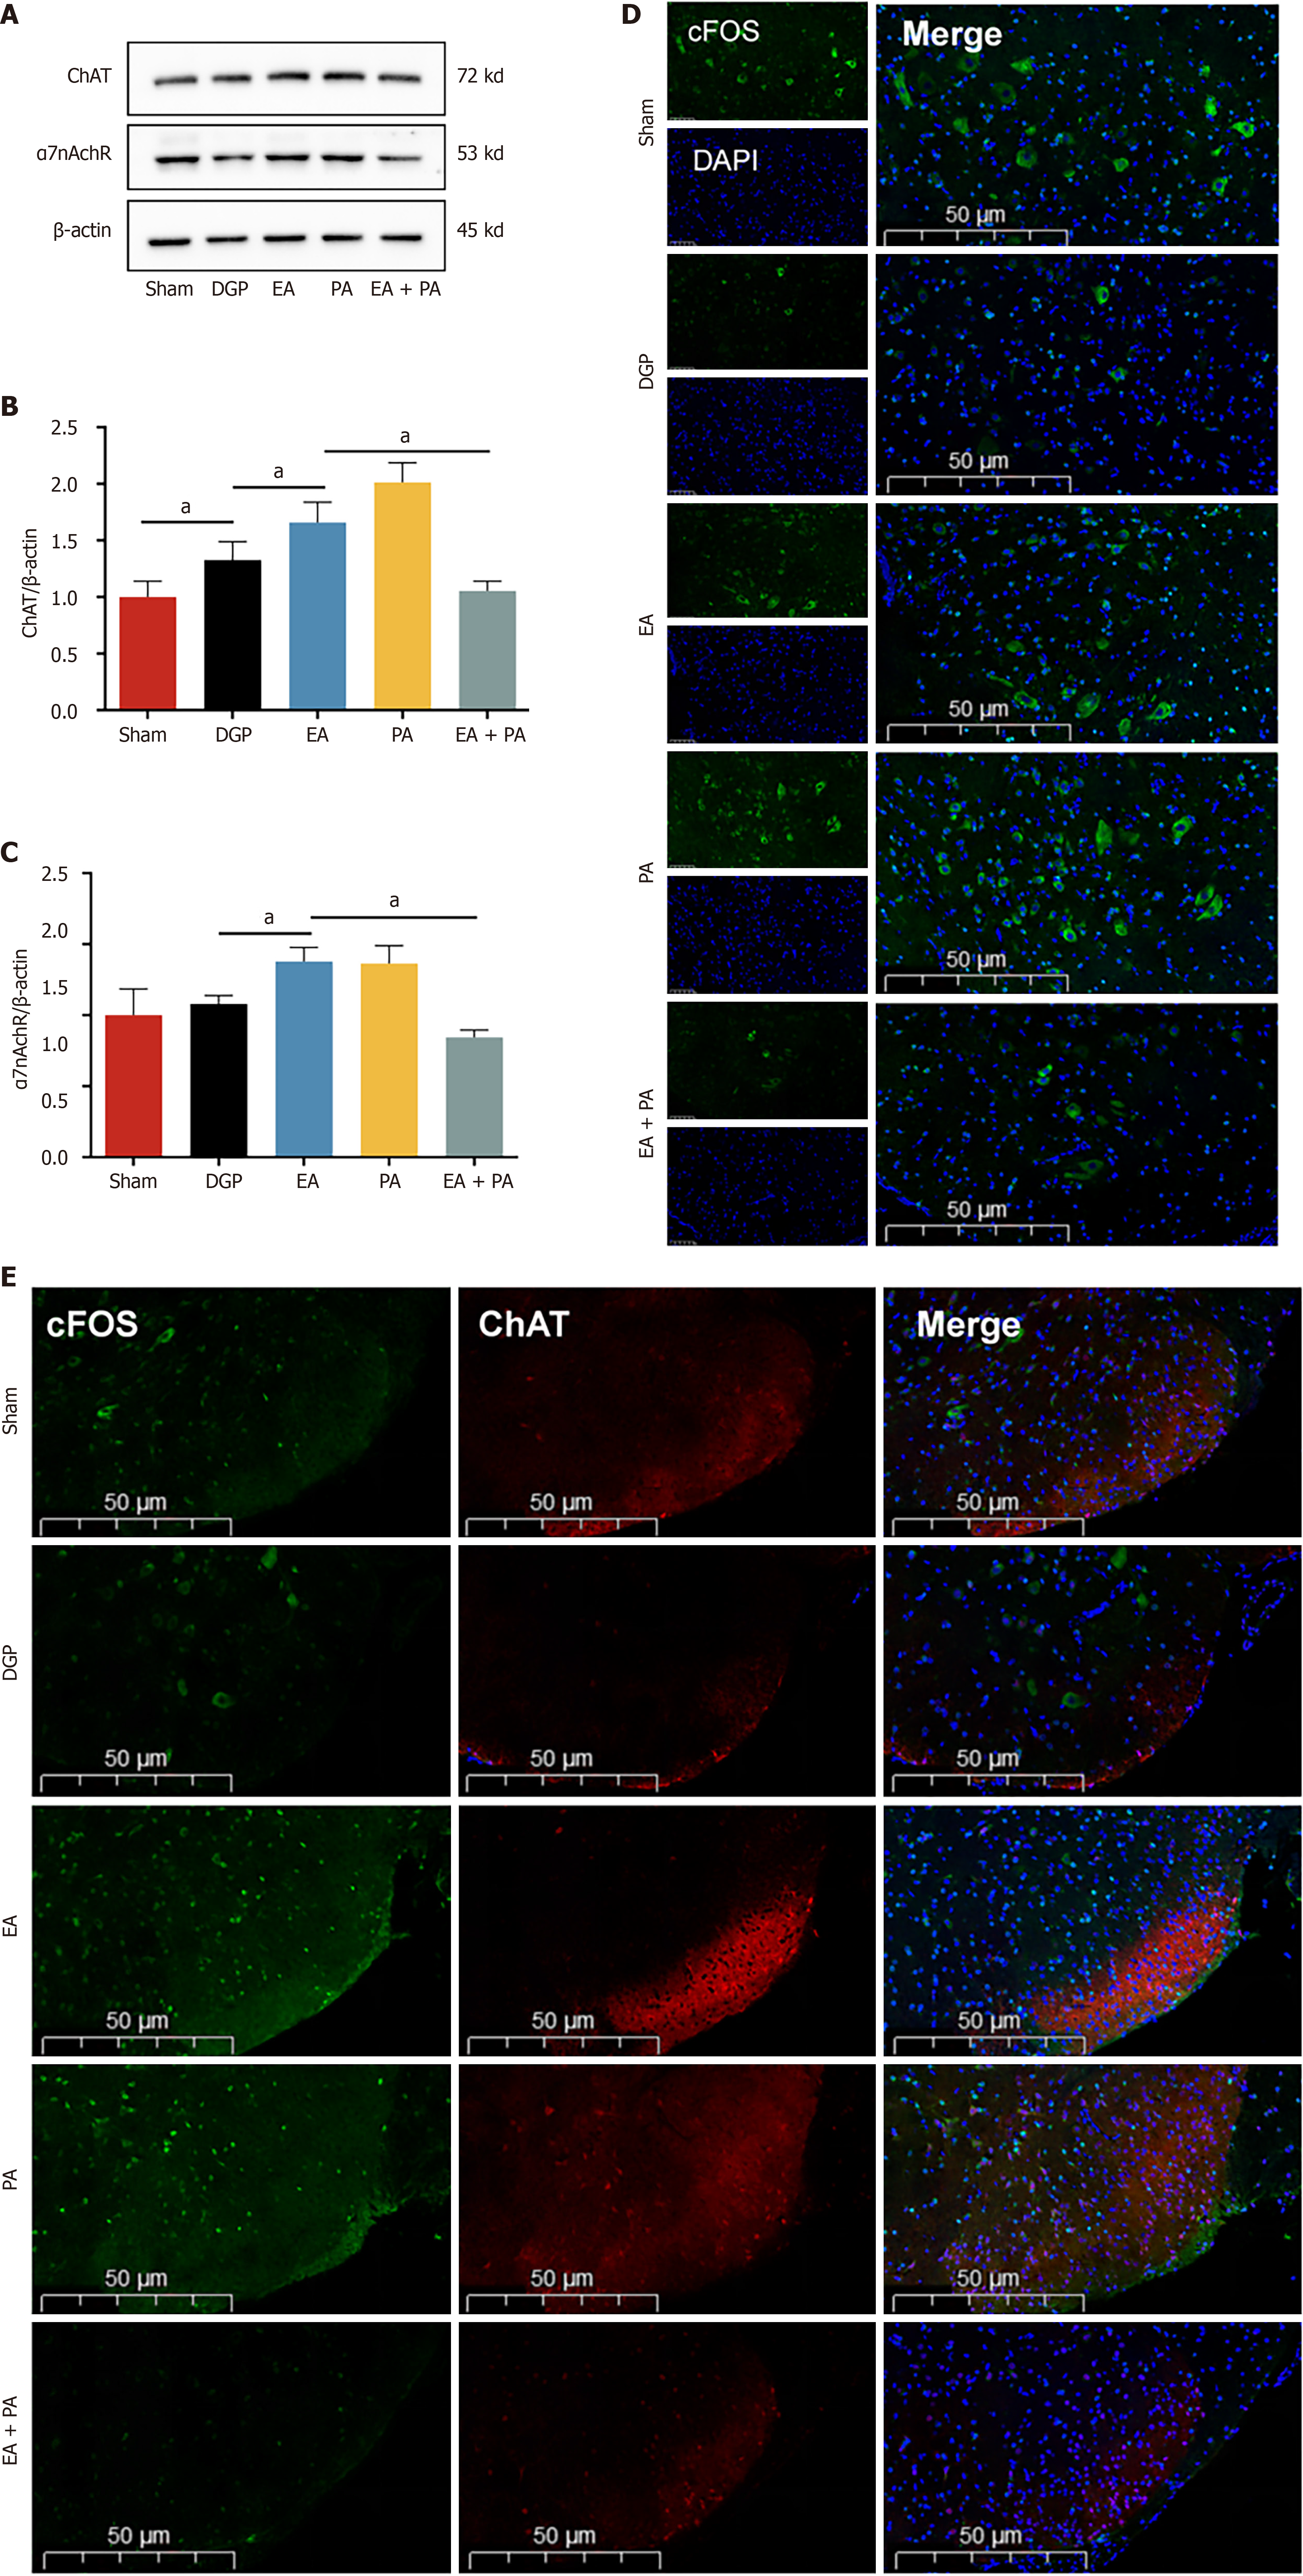

In order to elucidate the afferent neural pathways underlying EA-mediated gastric motility modulation in DGP rats, the ChAT inhibitor AP or the agonist PA was injected into the ST36 acupoint area and ChAT and α7nAChR protein expression was quantified across three key sites (Figures 4, 5 and 6): The ST36 acupoint skin, the spinal L4-L6 segments and the NTS (Figures 4A, 5A and 6A). Western blot analysis revealed significantly elevated ChAT levels in DGP rats compared to Sham controls across all sites (P < 0.05), with EA further amplifying ChAT expression (P < 0.05), mirroring trends observed in the PA group. However, the co-administration of AP with EA (EA + AP group) led to the abolition of this activation (P < 0.05; Figures 4B, 5B and 6B). In addition, EA induced an increase in α7nAChR expression in the ST36 skin, L4-L6 spinal region, and NTS (P < 0.05), an effect that was attenuated by AP co-treatment (P < 0.05; Figures 4C, 5C and 6C). Immunofluorescence analysis corroborated these observations. DGP rats exhibited reduced ChAT expression in ST36 skin, whereas EA and PA groups showed marked increases. AP administration nullified EA’s effects (Figure 4D). In the spinal L4-L6 segments, c-FOS immunostaining revealed robust neuronal activation in the EA and PA groups (P < 0.05), which was suppressed in the EA + AP rats (P < 0.05; Figure 5D). c-FOS +/ChAT + co-localization further confirmed that this activation was ChAT-dependent (Figure 5E). In the NTS, c-FOS expression was significantly elevated in the EA and PA groups (P < 0.05), with EA + AP rats showing reduced activation (P < 0.05; Figure 6D). c-FOS +/ChAT + co-expression mirrored these trends, demonstrating EA’s dual modulation of neuronal activity and cholinergic signalling (Figure 6E). The data taken together indicate that EA activates vagal ChAT/α7nAChR targets at ST36, transmitting signals via spinal L4-L6 afferents to NTS neurons, thereby restoring vagal tone in DGP.